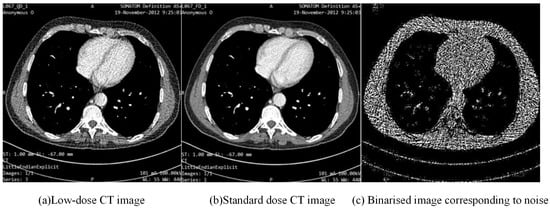

As shown in Figure 7, the input of the noise extraction network module is an LDCT image, and the output is the corresponding noise distribution map. In order to show the distribution of noise more intuitively, we binarized the noise features and generated a clear noise distribution map. The CT images input to the network are pre-processed low-dose scan data. These images introduce significant noise during the imaging process, and as the input of the network, the purpose is to extract and suppress this noise through network processing. The output label is the binarization result of the noise in the LDCT image. By representing the noise part in the form of a binary map, the network can more intuitively learn and identify the distribution characteristics of the noise.

Figure 7.

Input and label images for the noise extraction network.